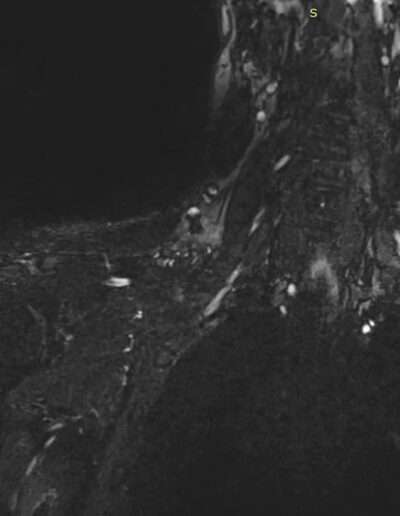

• 09/2023: Motorcycle accident → Brachial plexus injury (C5–C7)

• 3. BUT no glenohumeral active mobility and stability → NON-functional shoulder → Impossible use of the hand